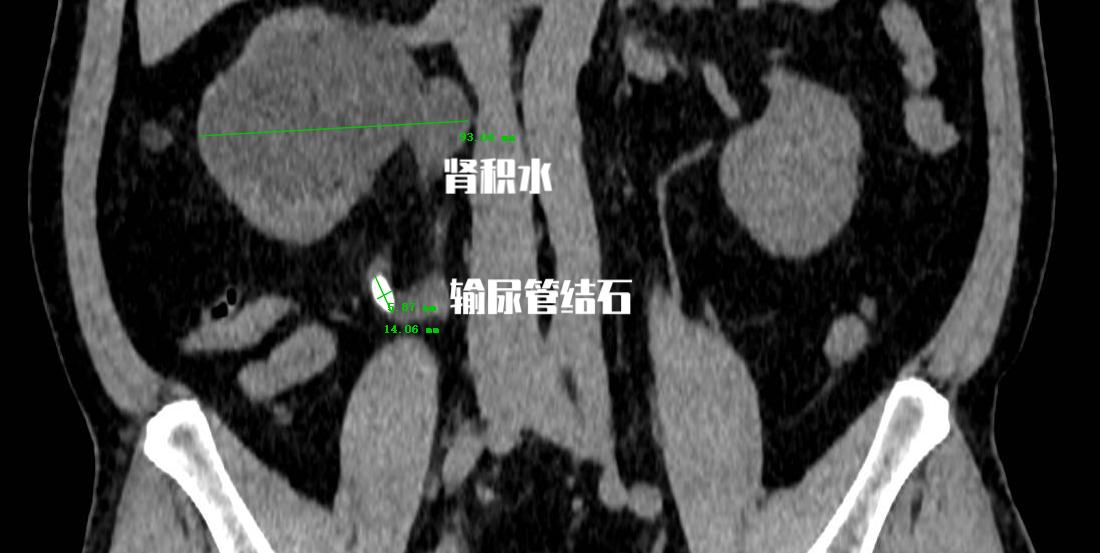

老李今年47岁,昨天体检发现 输尿管上端结石 ,但是他很奇怪的是基本不疼不痒,也没有任何症状。但是既然发现问题了,就到门诊做了CT检查提示: 右侧输尿管上端结石,长度约1.4cm,同时肾脏已经出现重度积水情况。

虽然老李没有任何症状,但是从CT片子上反映出老李的结石肯定已经堵塞了很长时间了,不光是出现了重度肾积水, 肾功能的指标中也已经出现了肾功能的损伤 ,所以当天急诊就做了输尿管结石手术。